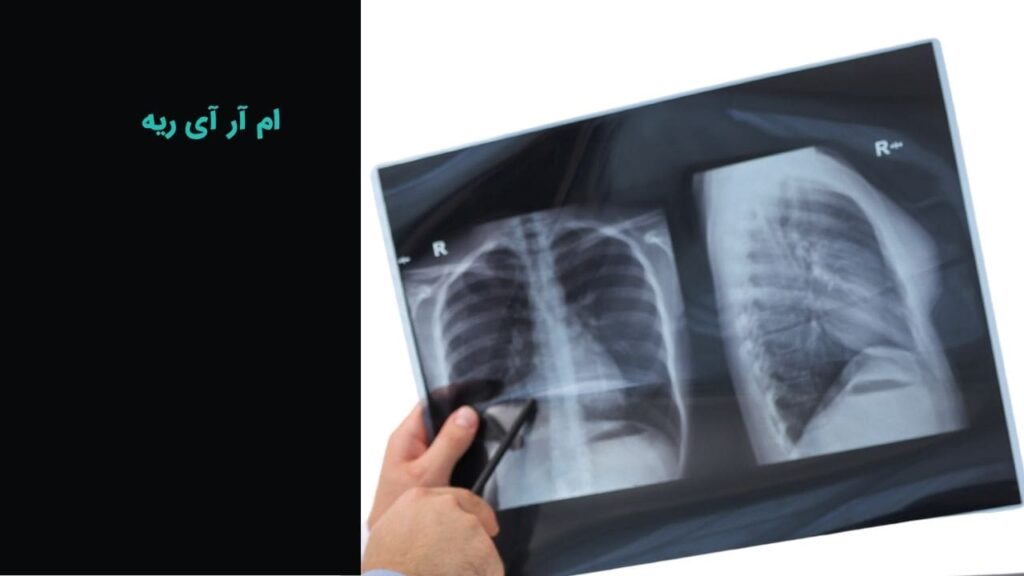

ام آر آی

ام آر آی عمومی و تخصصی با دستگاه 1.5 تسلا